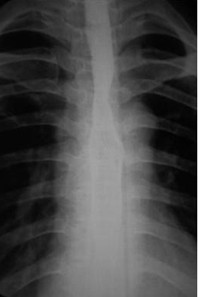

女,51岁,以“进行性吞咽困难1年”为主诉于2007年2月19日入院。钡餐造影、胃镜示食管上段占位性病变,确诊为食道鳞癌(图1),拒绝手术,行放疗+今又生治疗。食道镜下瘤内注射今又生,1×1012VP/次/周×6,放疗在今又生注射3 d后开始,采用常规分割三野等中心照射,剂量65cGY。治疗结束后4周,食管X线、胸部CT显示肿瘤完全消退(图4-5)。

放疗结束4周后